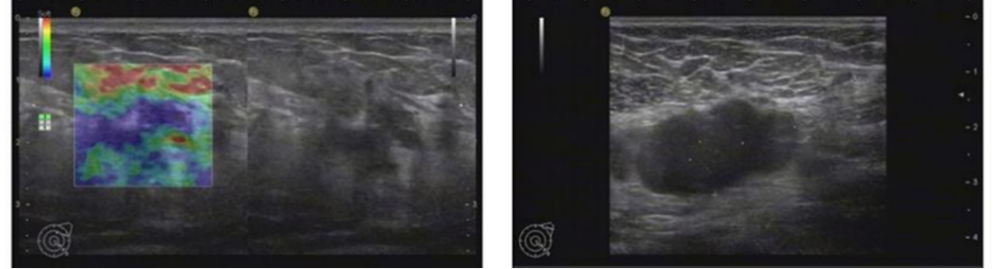

2021年6月颅脑增强MRI:左侧小脑占位,考虑转移瘤。

图2.颅脑增强MRI

2021年6月:出现头晕头痛1周,检查颅脑增强MRI:左侧小脑占位,考虑转移瘤。

2022年5月颅脑增强MRI:左侧小脑肿瘤切除术后改变。

疗效评价CR,继续维持曲妥珠单抗(汉曲优)+吡咯替尼+卡培他滨治疗方案

图3.颅脑增强MRI